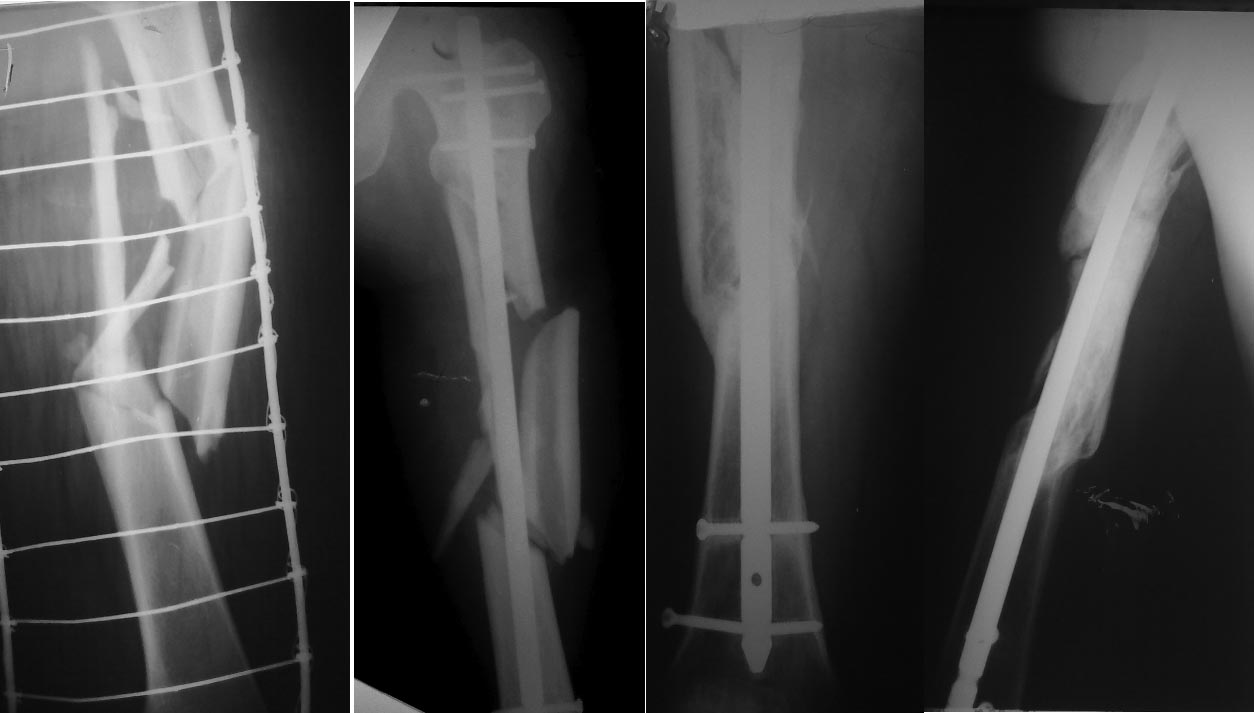

[Ortho] Итоги лечения многооскольчатого перелома бедра

Спасибо за предоставленный успешный результат лечения,был и у нас

сомнительный случай,однако от дополнительных вмешательств воздержались.